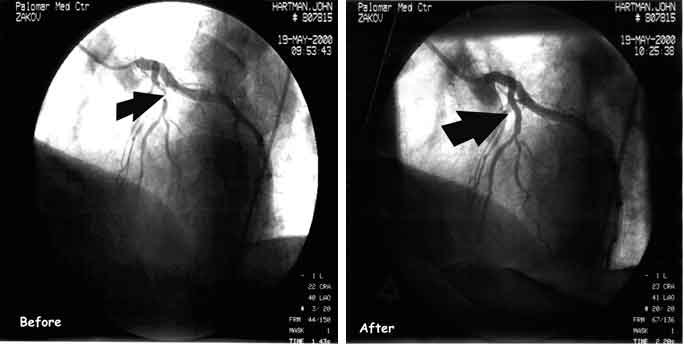

As was noted in the above text, N5AAA missed the HamVention at

the last minute due to some surgery he had to have done. Below are a

before and after shots of the surgery area. Thank goodness for medical

technology!